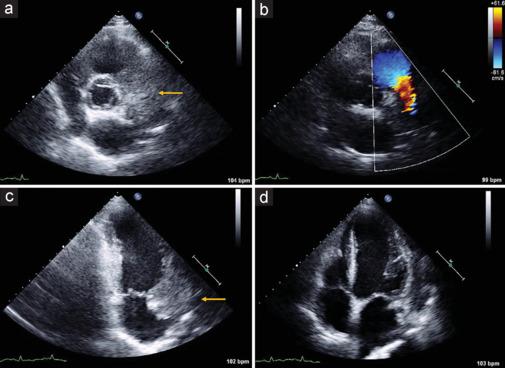

Cardiovascular disease and cancer constitute the most prevalent illnesses worldwide. Cancer patients show an increased risk of coronary artery disease not only due to shared cardiovascular risk factors, a pro-inflammatory and prothrombotic state induced by cancer itself, the cardiovascular toxicity of cancer therapy, or rarely, due to extrinsic compression of a coronary artery by the primary tumor or a metastatic lesion. Here, we present the case of a 59-year-old man with squamous cell carcinoma of the lung presented with asymptomatic diffuse ST segment depression and troponin T increase. Echocardiography revealed a large mass adjacent to the right atrium, atrioventricular groove, and basal segment of the anterior wall of the left ventricle, which the computed tomography scan showed to encase and probably compress the anterior descending coronary artery. Thus, the patient was diagnosed with acute coronary syndrome due to anterior descendent coronary artery compression by a neoplastic lung mass.

心血管疾病和癌症是全球最常见的疾病。癌症患者患冠状动脉疾病的风险增加,这不仅是由于共同的心血管危险因素、癌症本身引发的促炎和促血栓状态、癌症治疗的心血管毒性,或者很少见的情况,即原发性肿瘤或转移病灶对冠状动脉的外在压迫。在此,我们报告一例59岁男性肺鳞状细胞癌患者,其表现为无症状的弥漫性ST段压低和肌钙蛋白T升高。超声心动图显示右心房、房室沟和左心室前壁基底段附近有一个大肿块,计算机断层扫描显示该肿块包裹并可能压迫前降支冠状动脉。因此,该患者被诊断为因肺部肿瘤压迫前降支冠状动脉导致的急性冠状动脉综合征。